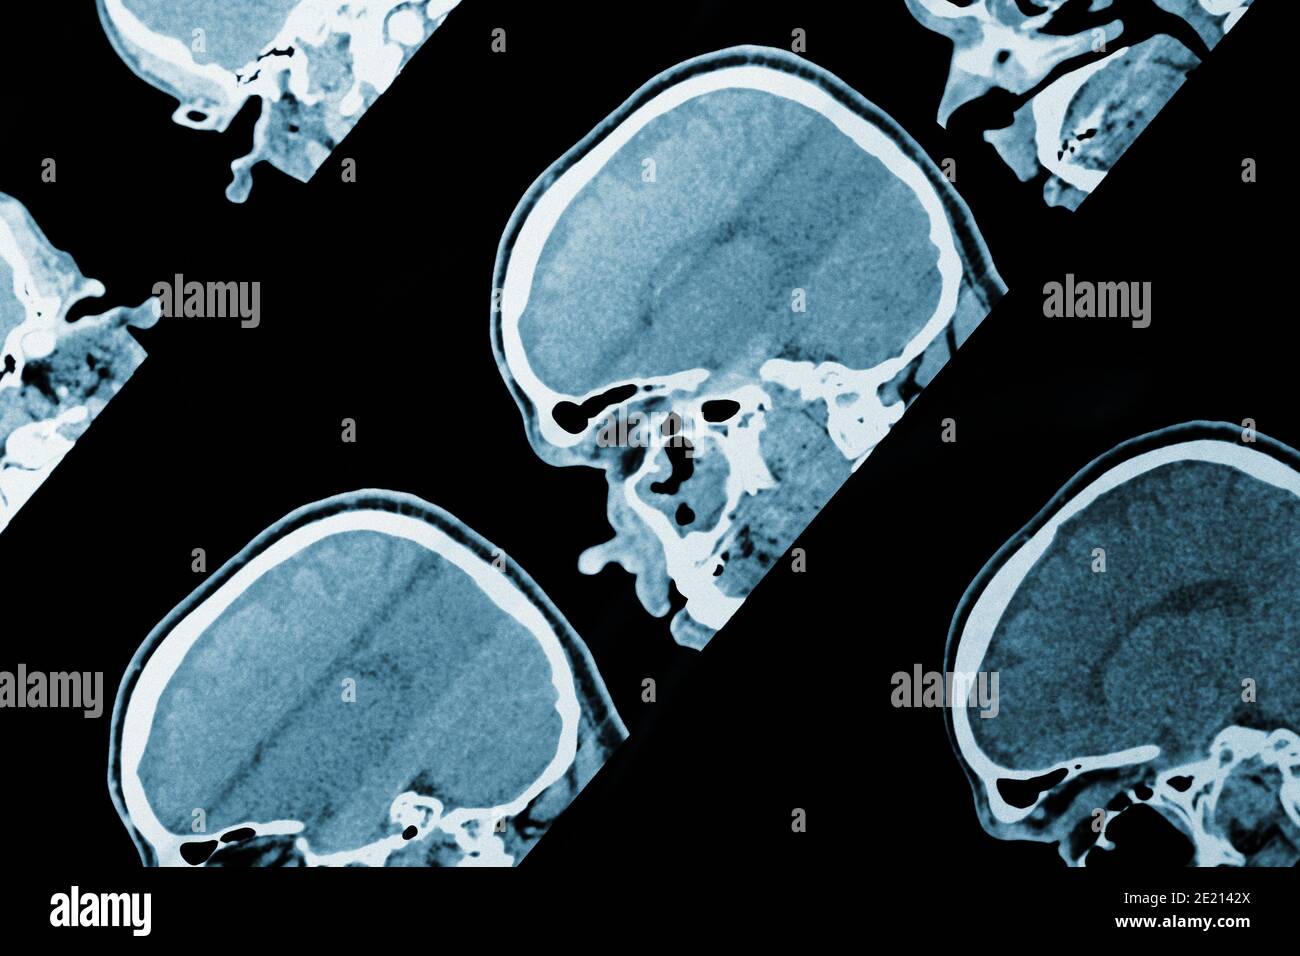

Image IRM de la tête comme arrière-plan médical. Banque D'Imageshttps://www.alamyimages.fr/image-license-details/?v=1https://www.alamyimages.fr/image-irm-de-la-tete-comme-arriere-plan-medical-image397092946.html

Image IRM de la tête comme arrière-plan médical. Banque D'Imageshttps://www.alamyimages.fr/image-license-details/?v=1https://www.alamyimages.fr/image-irm-de-la-tete-comme-arriere-plan-medical-image397092946.htmlRF2E2142X–Image IRM de la tête comme arrière-plan médical.